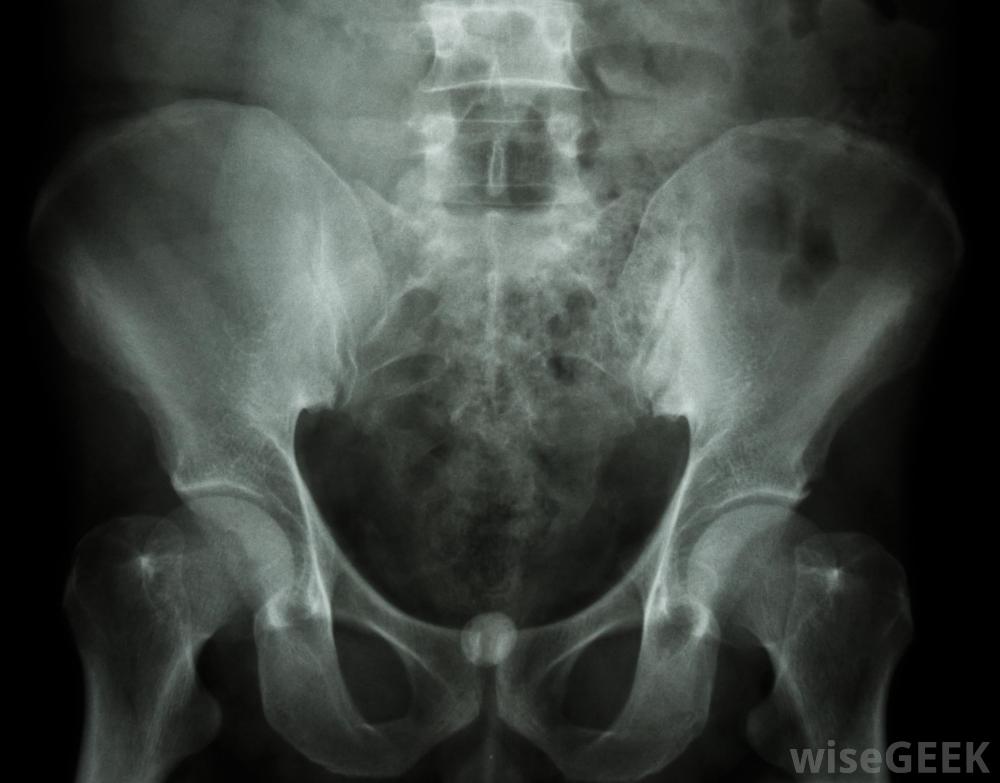

尿流计是一种诊断性试验,用于检查病人尿液的量或流速是否异常。该程序简单明了,无痛,只需将尿液放入电子量表上的漏斗装置中。医生通常使用尿流率来检查可能的膀胱阻塞,肾脏问题,前列腺肥大和尿路感染。不寻常的检查结果表明需要额外的检查程序,例如x光片和实验室样本分析。

尿流量测定的异常结果可能会导致额外的检查,比如X光。